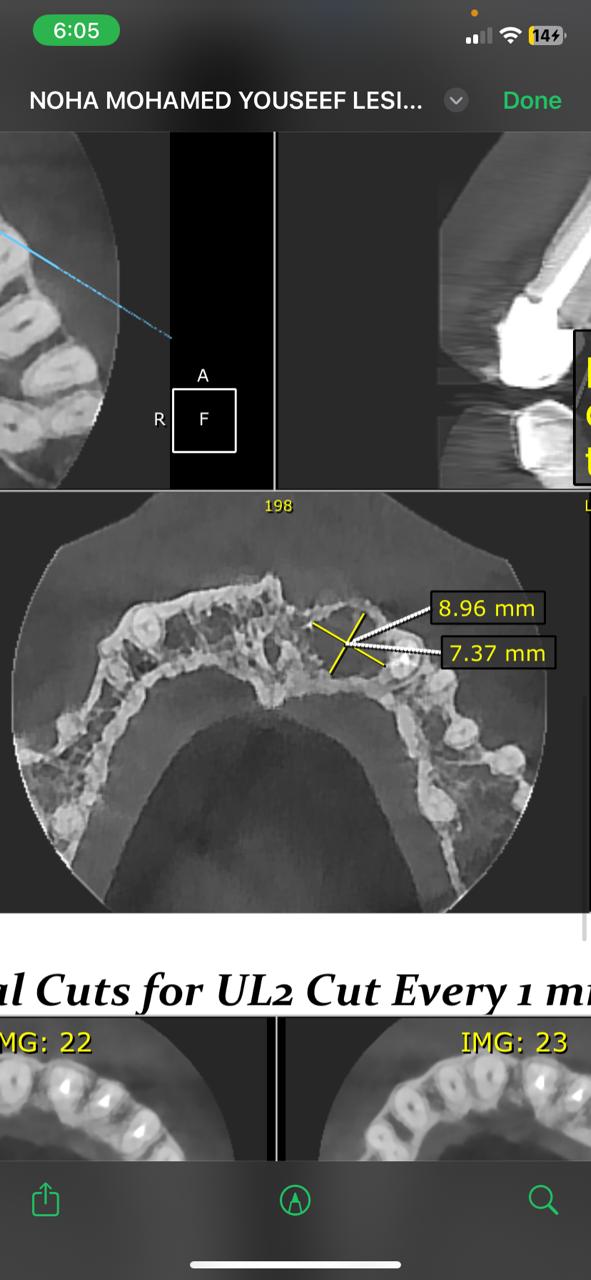

وأجرى الفريق الطبي بالمستشفى العملية بنجاح تحت التخدير الموضعي، حيث تم استئصال الكيس المرضي بالكامل من منطقة تحت القاطع الأول والثاني يسار الفك العلوي، واستغرقت الجراحة نحو ساعة ونصف دون مضاعفات.